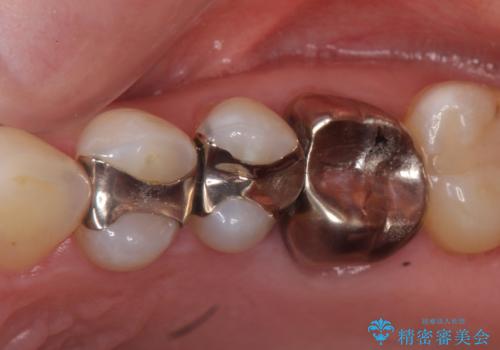

- 左上4、5、6番目の歯を白くしたいといらっしゃった方の症例です。

4番目の歯はセラミックインレーによる修復、5・6番目の歯はオールセラミッククラウンによる補綴を行いました。

左上6番目の歯については再根管治療を行っております。